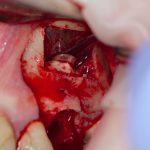

Установка имплантатов.

Напомню, что для этой работы я выбрал субкрестальные имплантаты Ankylos C/X. Они прекрасно сочетаются с любым методом остеопластики.

Я не планирую установку супраструктур или коронок, поэтому на уровень первичной стабильности можно положить болт. Даже наоборот — чем меньше крутящий момент при установке, тем лучше. Для имплантатов Ankylos и подобных им, это особенно важно. В общем, момент силы при установке — не более 10-15 Нсм.

Ремарка: имплантаты с предустановленными имплантодержателями хороши тем, что с ними легко контролировать позиционирование имплантатов. В случае с Ankylos С/Х - еще и крутящий момент. Имплантодержатель должен отсоединяться от имплантата с легким щелчком. Если его клинит, и тебе приходится прикладывать для этого усилия, то ты, однозначно, превысил момент силы во время установки имплантата. Следовательно, жди проблем.

Глянем на то, что получилось:

Осталось адаптировать костный блок (убрать острые края), проверить его фиксацию и, при необходимости, добавить винты. Десятисекундное дело.